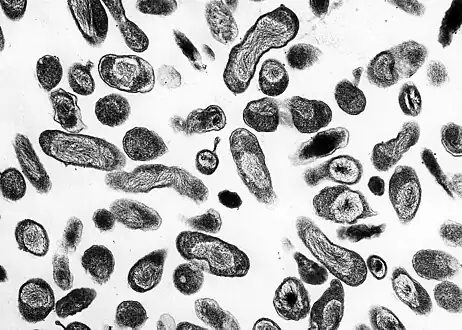

Photomicrograph of numerous, Gram-negative, Coxiella burnetii bacteria

Photomicrograph of numerous, Gram-negative, Coxiella burnetii bacteria C. burnetii, the Q fever-causing agent